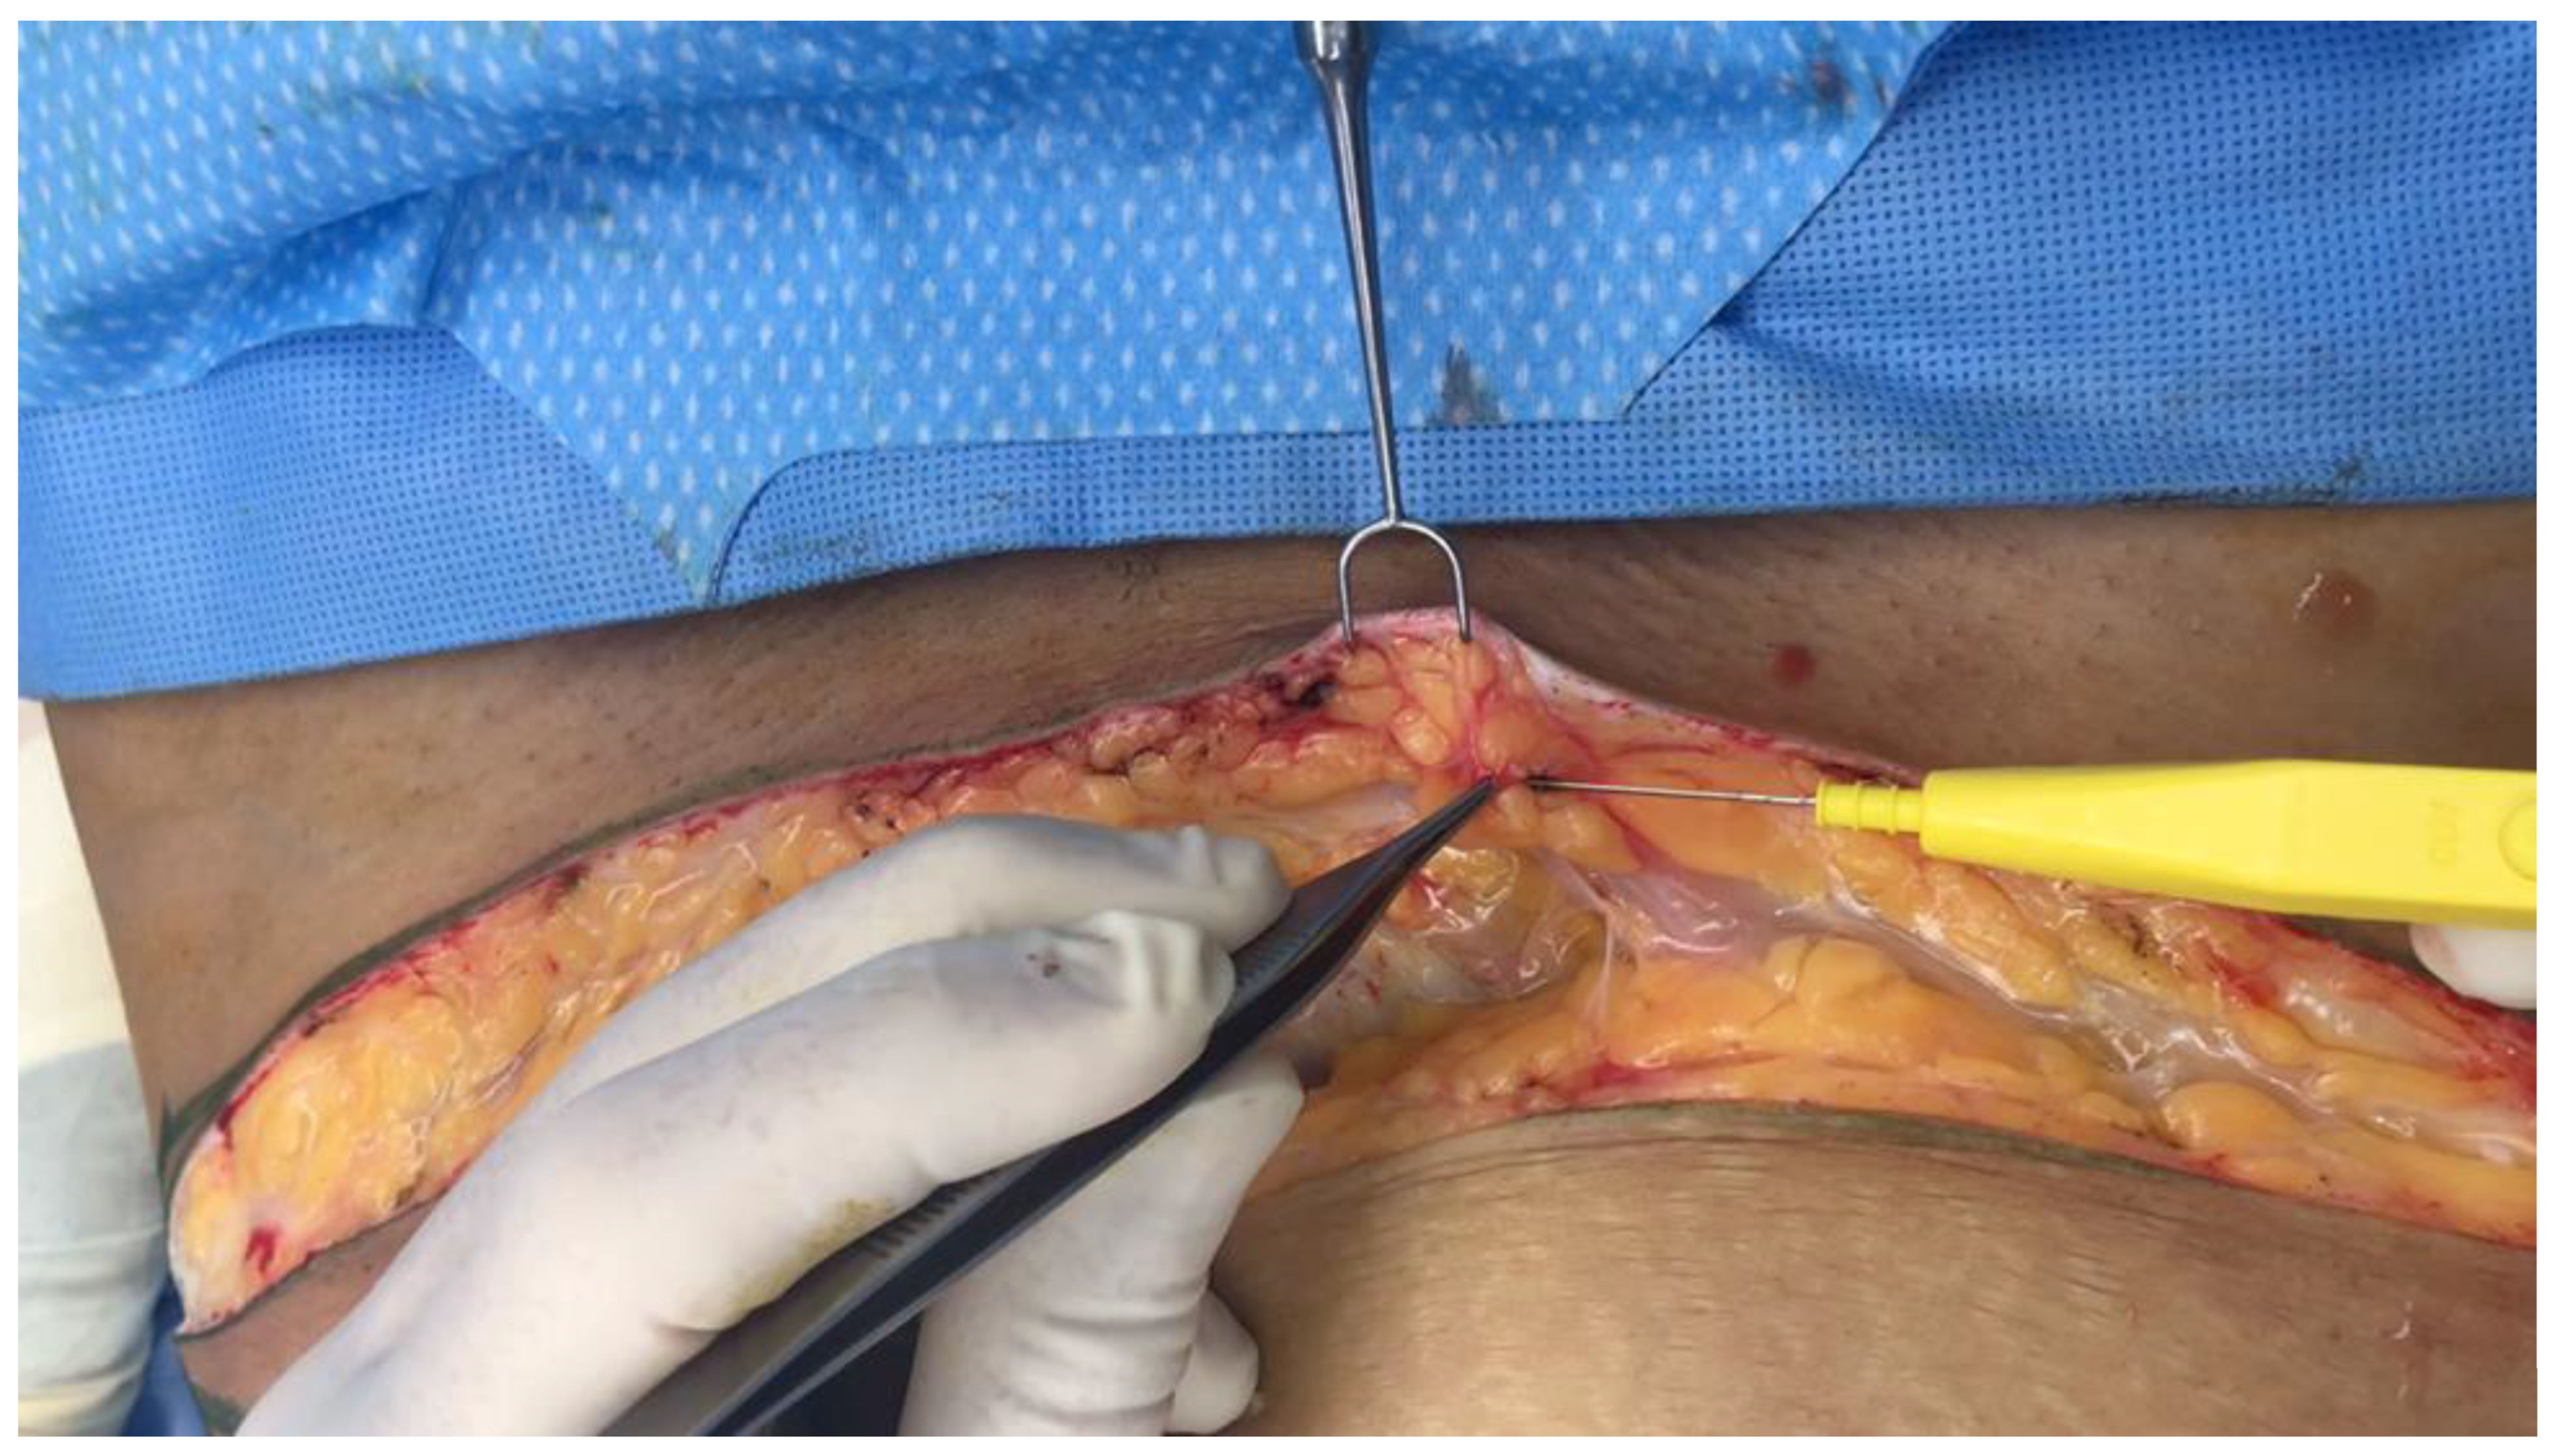

As discussed earlier in this paper, the use of dilute local-anesthetic solutions with epinephrine, known as tumescent anesthesia (typically 1000 cc of saline solution, 30 cc of lidocaine 1% solution, and 1 milligram of epinephrine) is commonly used in plastic and reconstructive surgery. The volume injected through needles in facelifts (250 cc) is smaller than the large volumes (1–4 L) injected in liposuction, breast surgery, and abdominoplasty (Figure 10).

Figure 10. Abdominoplasty procedure with the pannus being resected and retracted upwards, away from the low abdominal incision in the lower right of the picture. Tumescent local anesthetic fills the interstitial space below the white Scarpa’s fascia, seen in the lower left of the picture. The clear, loose, areolar connective tissue keeps the tumescent fluid from running out of the wound.